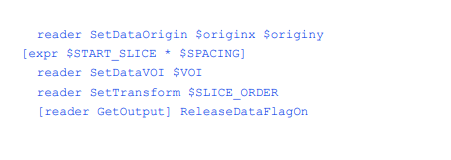

我们在这里假设所有要处理的数据都是通过一个恒定的中心地标获得的。在VTK中,数据的原点应用于图像卷的左下角。在这个管道中,我们计算的原点是体积的x,y中心为(0,0)。dataspace描述了每个像素的大小和片之间的距离。DataVOI选择感兴趣的卷(VOI)。VOI可以让我们选择感兴趣的区域,有时可以消除无关的结构,如CT台床。对于青蛙,我们编写了一个小的C程序来读取组织标签文件,并为每个组织找到感兴趣的体积。

SetTransform()方法定义了如何在内存中排列数据。医学图像可以以不同的顺序获得。例如,在CT中,数据可以从上到下(上级到下级)收集,也可以从下到上(下级到上级)收集。此外,MRI数据可以从左到右、从右到左、从前到后(前到后)或从后到前获取。这个过滤器转换三角形顶点,这样得到的模型都将“面向”观看者,视角向上(0,-1,0),向下看正z轴。同时,保持适当的左右对应关系。这意味着病人的左侧将始终留在生成的模型上。查看SliceOrder。TCL来查看每个顺序的排列和旋转。

所有其他参数都是不言自明的,除了最后一个。在这个脚本中,我们知道管道将只执行一次。为了节省内存,我们调用ReleaseDataFlagOn()方法。这允许VTK管道在过滤器处理完数据后释放数据。对于大型医疗数据集,这可能意味着是否能够处理数据集之间的差异。